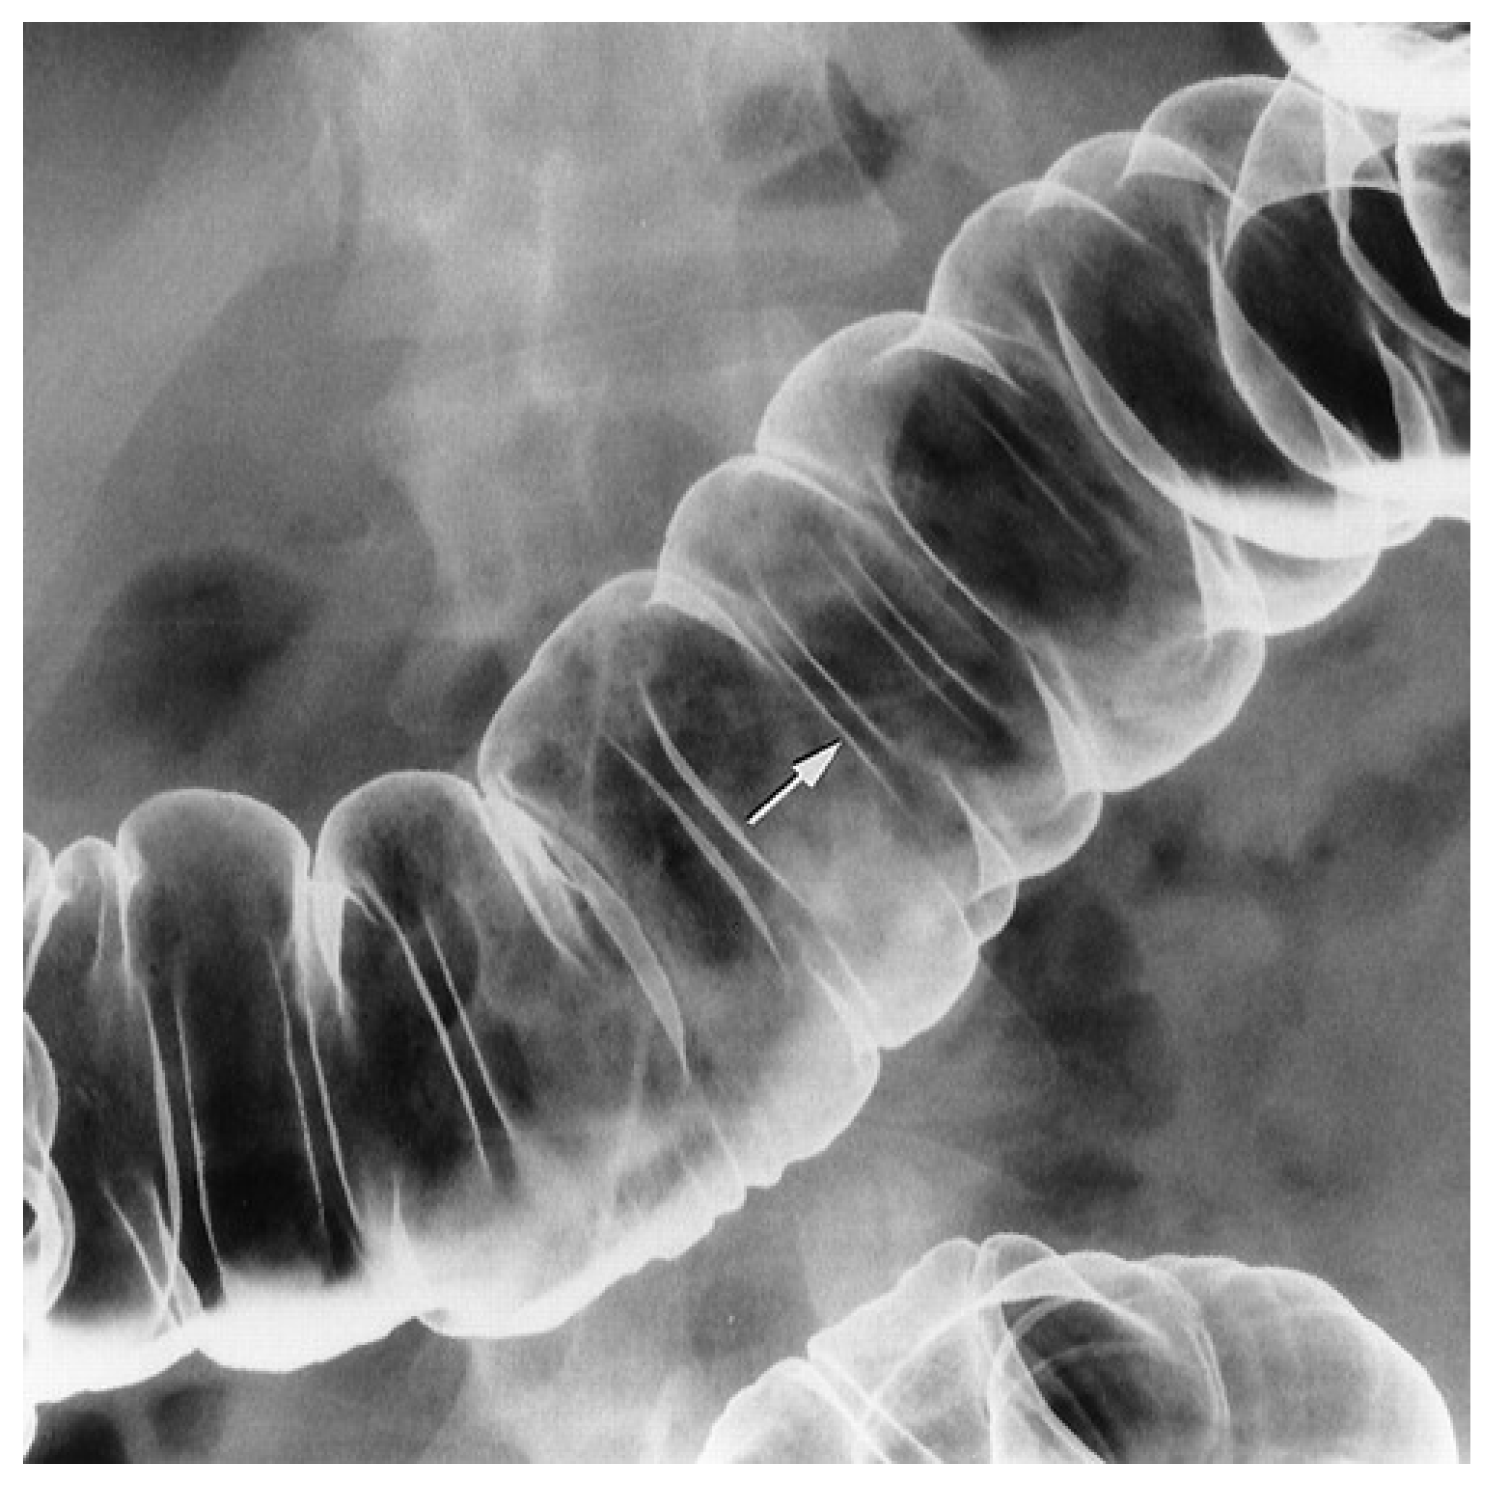

- Maglinte, D.D.; Elmore, M.F.; Isenberg, M.; Dolan, P.A. Meckel diverticulum: Radiologic demonstration by enteroclysis. AJR Am. J. Roentgenol. 1980, 134, 925–932. [Google Scholar] [CrossRef]

- Thurley, P.D.; Halliday, K.E.; Somers, J.M.; Al-Daraji, W.I.; Ilyas, M.; Broderick, N.J. Radiological features of Meckel’s diverticulum and its complications. Clin. Radiol. 2009, 64, 109–118. [Google Scholar] [CrossRef]